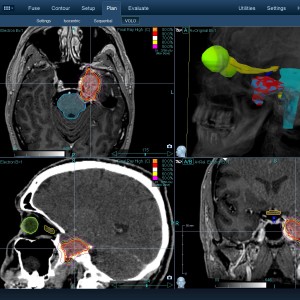

Στις παρακάτω φωτογραφίες θα δείτε παραδείγματα πλάνων θεραπείας καρκινικών όγκων με CyberKnife. Παρατηρήστε πόσο κοντά στους υγιείς ιστούς βρίσκονται οι καρκινικοί όγκοι που χρειάζεται να ακτινοβοληθούν. Μόνο με το CyberKnife και το προσωπικό πλάνο θεραπείας, μπορούν να ακτινοβοληθούν οι όγκοι χωρίς να πληγούν οι παρακείμενοι υγιείς ιστοί.

Μόνο με το CyberKnife και την κατάλληλη σχεδίαση της θεραπείας από έμπειρο νευροχειρουργό, μπορεί να ακτινοβοληθούν οι όγκοι χωρίς να επηρεαστούν από την ακτινοβολία οι υγιείς ιστοί. Αυτό εξασφαλίζει τη μέγιστη δυνατή απόδοση της ακτινοχειρουργικής θεραπείας των όγκων.

Με κόκκινο χρώμα περιγράφεται η περιοχή του όγκου.

Με μπλε, κίτρινο και πράσινο χρώμα περιγράφονται οι υγιείς ιστοί που δεν πρέπει να ακτινοβοληθούν.

Παρατηρήστε πόσο κοντά βρίσκεται ο όγκος με τους υγιείς ιστούς.